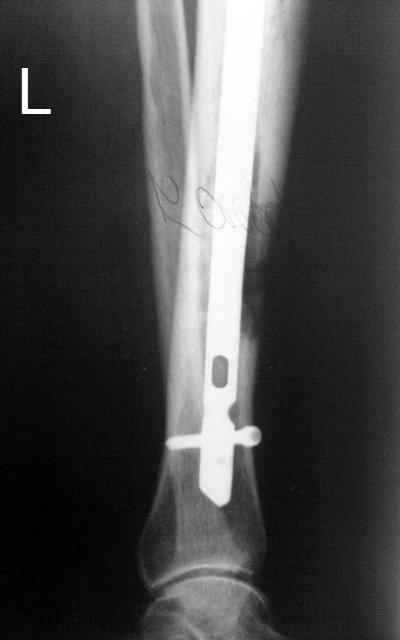

Выкладываю картинки похожей пациентки. Извините, что без окончательных снимков (сейчас их нет под рукой). Правда мы имели проблемы у данной больной после снятия аппарата, когда промежуточный фрагмент большеберцовой кости сместился на 1,5 см дистально и отошел от проксимальной части кости. До сих пор у пациентки на снимках определяется лишь тонкая полоска кости по задней поверхности за штифтом (образовалось что-то вроде маленького регенерата)в области стыковки промежуточного и проксимального фрагментов. Больная пока решила подождать. Не хочет оперироваться, так как ходит не хромая, работает.